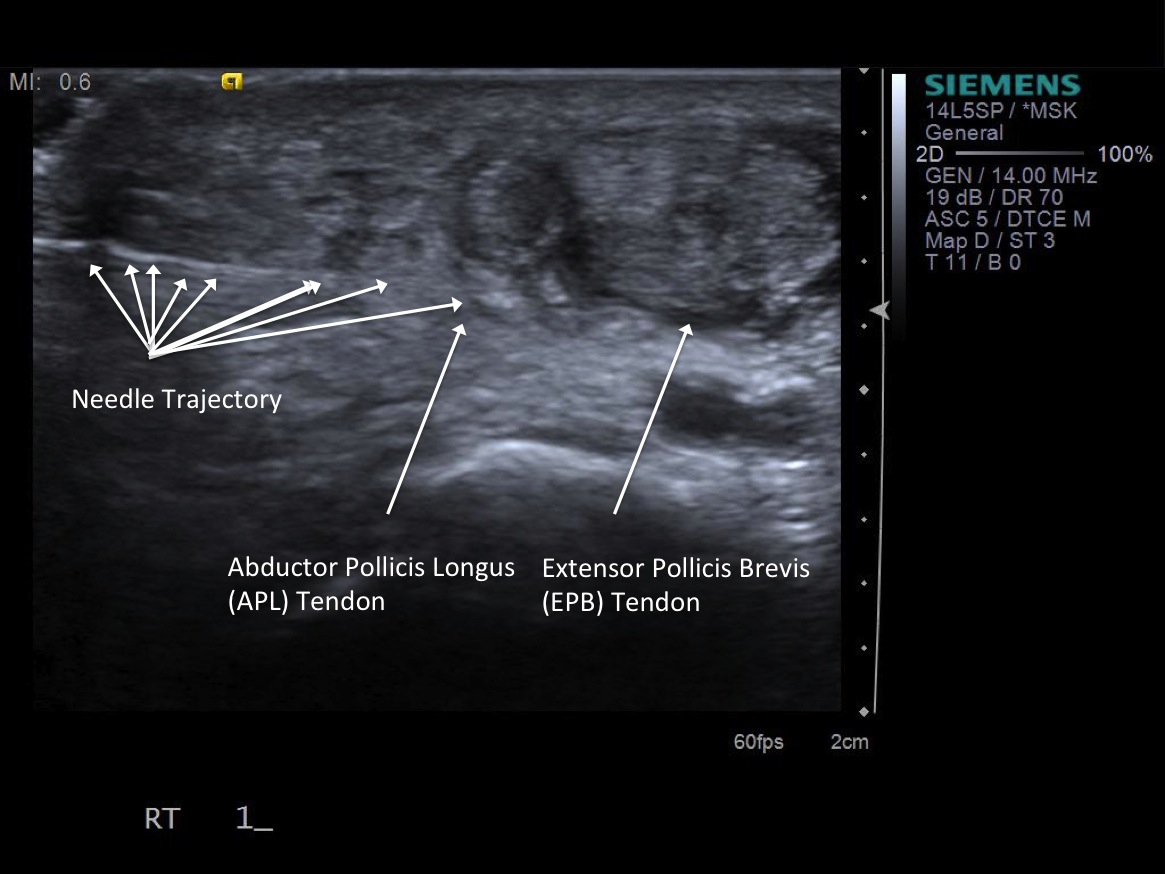

3. Place probe in short axis over first comparment extensor tendons-- Extensor pollicis brevis and abductor pollicis longus. description description

6. Inject 1% lidocaine superficially with 25g 1.5” needle. Advance needle deeper surface of the 1st extensor tendon sheath. Oftentimes, the APL and EPB tendons are in separate sheaths and may require separate injections. Then, unscrew syringe from needle for greater needle control.

7. Under ultrasound guidance,advance needle into the 1st extensor tendon sheath. In this case the APL and EPB have separate sheaths and require their own injections. Test inject with 1% lidocaine. If no resistance, switch 1% lidocaine for injectable steroid mixture. If there is resistance, reposition needle and test inject again. Inject 1 cc of injectable steroid/anesthetic mixture.